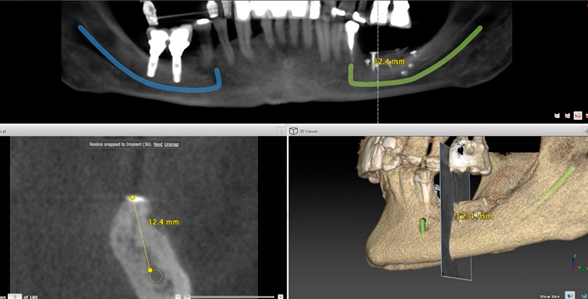

As figuras, abaixo, demonstram 3 exemplos clínicos de ROG vertical, onde foi utilizado osso autógeno particulado e substituto ósseo xenógeno, na proporção 1:1, cobertos com a membrana Cytoplast, fixada com miniparafusos. Na figura 1, temos um caso de aumento ósseo vertical, em região posterior de mandíbula, sem utilização de parafuso tenda. Na figura 2, um outro caso de aumento vertical, também em região posterior de mandíbula, onde o uso do parafuso tenda foi essencial em uma localização do defeito, corroborando o reforço de titânio da membrana. Na figura 3, temos um caso de aumento vertical na região anterior de maxila, onde o parafuso tenda foi utilizado, em um ponto considerado crítico para reconstrução óssea requerida.

Figura 1:

Figura 2: